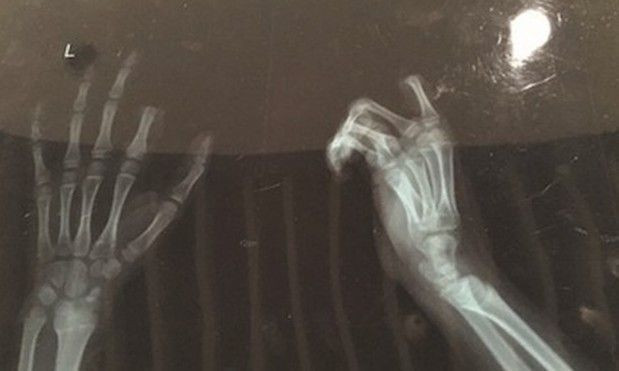

Ảnh chụp X-quang cho thấy đầu ngón trỏ trên bàn tay trái của Xiaopeng đã bị cắt rời.

Quá tức giận trước hình phạt của cha mẹ, Xiaopeng đã xuống bếp, sử dụng dao và cắt đứt ngón tay trỏ trên bàn tay trái của mình như một cách để hù dọa cha mẹ.

Các bác sĩ đã phải mất 3 giờ phẫu thuật để cố gắng nối lại đầu ngón tay cho Xiaopeng, tuy nhiên hiện vẫn chưa rõ ca phẫu thuật có giúp cho ngón tay hoạt động lại bình thường như trước hay không do trẻ em có mạch máu lớn hơn nên gặp nhiều khó khăn hơn trong việc phẫu thuật nối liền chi. Hiện Xiaopeng vẫn đang phải theo dõi tích cực trong bệnh viện sau ca phẫu thuật.